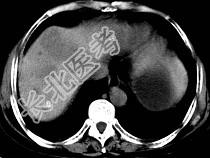

- 单项选择题女,55岁, 腹胀,肛门闭气, 消瘦乏力,肝区疼痛, CT检查如图,最可能的诊断为 ( )

A、多发性肝脓肿

B、肝癌肝内转移

C、肝淋巴管瘤

D、肝脏囊腺瘤

E、结肠癌肝转移